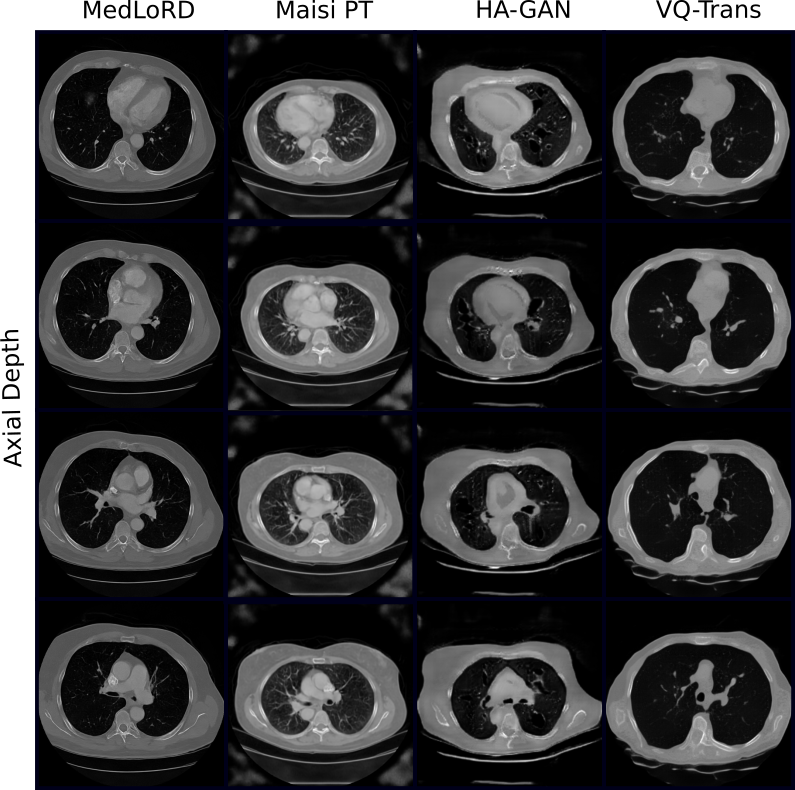

Refer to caption

(b) Randomly selected unconditional Luna samples (axial view).

Figure A2: Randomly selected unconditional samples from PCCTA and Luna datasets.

First, we conducted unconditional image synthesis. Fig. 2 shows representative samples from both the PCCTA and LUNA datasets. MedLoRD consistently generates high-quality, realistic images, preserving both global and local structural details. In contrast, other models exhibited unstable behavior, with some samples showing poor quality and heavy artifacts (e.g., loss of heart structures in MAISIST, poor realism in HA-GAN; see Fig. 2(a)). VQ-Trans and MAISIPT showed partial success, though the latter still displayed artifacts in PCCTA samples.